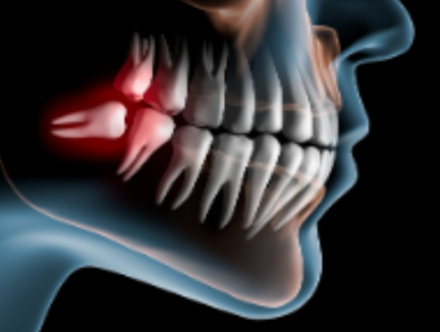

親知らずの知識

親知らずは全て抜いたほうが良いのか?